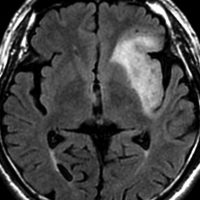

2010年無症状の時の画像です。こんなのを手術で摘出したら認知機能が落ちて人格が変わります。だから経過観察しました。

2015年のテモゾロマイドを開始する前の画像です。2014年にちょびっと生検術をして1p/19q欠失,IDH変異はわかっていました。2015年に全般発作を起こしたので治療を開始しました。テモゾロマイドを 2年 24コース続けました。乏突起膠腫は大きくなる時,てんかんを生じることが多いです。

2020年の画像です。腫瘍はかなり小さくなって再燃(再発)していません。てんかんも抑制されて発作はありません。無症状です。

この例は,手術も放射線治療もしないで,乏突起膠腫が10年以上,制御できることを示しています。また,テモゾロマイド治療でてんかん発作が少なくなることも有名な事実です。

でも,現実はこんなに甘くない?  2025年時点で,治癒を目指すなら低線量放射線治療を加えるべきと考えられています。